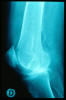

Fractura impactada de húmero .